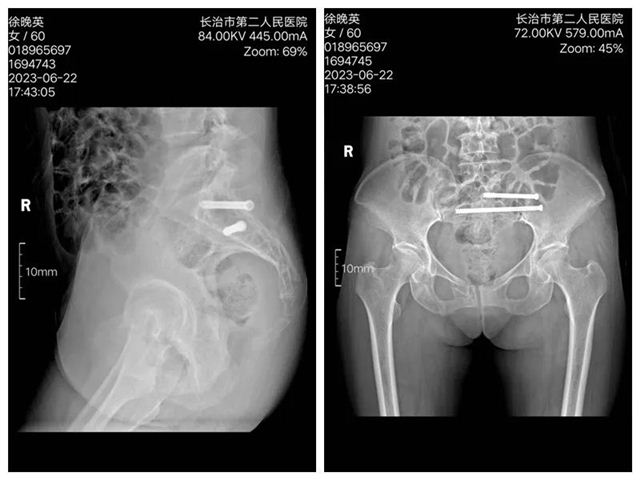

近日,长治二院创伤骨科二病区在智能骨科手术机器人辅助下,成功为两位骶骨、耻骨骨折患者实施手术。 病 例 一 术前影像 入院后,李黎明主任团队综合评估病情,为充分减少创伤,更加利于患者术后康复,决定应用更加先进、更加精准的骨科手术机器人辅助下的微创技术,为徐某行机器人辅助下骨盆骨折闭合复位内固定术。 手术过程中,李黎明主任,徐彦芳医生通过调整透视定位后将骨盆透视影像导入机器人操作界面,在该界面,根据扫描影像规划骶髂螺钉置入位置、方向、长度等数值,在导航系统引导下,经皮小切口精准置入S1,S2通道螺纹导针。经C型臂透视后证实骨折复位满意,导针位置好后,拧入规划长度的螺钉。 术后影像 病例二 术前影像 术后影像 骨科创伤二病区李黎明主任表示,智能骨科手术机器人集合了人工智能、精准手术、安全微创等特色,优势明显。特别是遇到复杂疑难的手术时,利用影像学精准建模,经过术前规划确定骨折位置,明确置入位置和角度,在术中利用灵活的机械臂进行实时定位图像导航,确保螺钉的实际置入零误差,大大降低了术中的风险。 据了解,自2021年10月“天玑”骨科手术机器人投入使用以来,我院骨科共为76名,骨折、骨伤患者成功实施了手术。